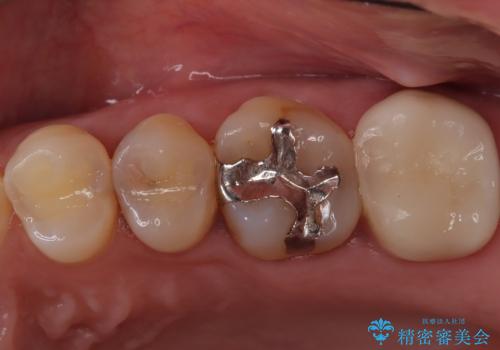

目立つ銀歯と欠けてしまった詰め物 オールセラミッククラウンでの補綴治療

不快感の強い奥歯 オールセラミッククラウンでのむし歯治療